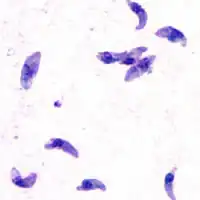

| Tacozoítos de T. gondii | |

Toxoplasmose é uma doença parasitária causada pelo protozoário Toxoplasma gondii.[4] As infeções de toxoplasmose geralmente não causam sintomas óbvios em adultos.[2] Em alguns casos pode ocorrer síndrome gripal ligeira durante algumas semanas ou meses, com sintomas como dor muscular e sensibilidade nos gânglios linfáticos.[1] Numa pequena percentagem de pessoas podem-se desenvolver problemas de visão.[1] No sul do Brasil, segundo estudos iniciados na década de 1990, uma parcela significativa da população teve contato com o Toxoplasma gondii (cerca de 80 %), causando lesões oculares que podem causar a cegueira em um grande número de pessoas (17,7 %)[8]. Em pessoas imunossuprimidas, podem ocorrer sintomas graves, como crise epilépticas ou falta de coordenação motora.[1] Quando a primeira infeção ocorre durante a gravidez, a doença pode ser transmitida de mãe para filho pela placenta, uma condição denominada toxoplasmose congénita.[1] A toxoplasmose congénita está associada a morte fetal e aborto espontâneo e, em crianças, está associada a déficits neurológicos, neurocognitivos e corioretinite.[3]

O Toxoplasma gondii é um protozoário parasita intracelular obrigatório do grupo dos Apicomplexa, como outros parasitas como o Plasmodium. Há pouca variação entre os toxoplasmas presentes em diferentes partes do globo, podendo-se dizer que há, basicamente, três estirpes. A cepa 1 é altamente virulenta e responsável pelos casos de encefalite grave em imunodeprimidos e passagem transplacentária. As cepas 2 e 3 são avirulentas. As cepas 1, 2 e 3 são comuns na Europa e nos Estados Unidos. Mesmo a cepa 1, a mais agressiva das três, não causa tanto problemas oculares como as cepas atípicas, encontradas no sul do Brasil. Estas cepas atípicas são mais agressivas e causam lesões oculares em um grande número de pessoas. O surgimento destas cepas ocorreu possivelmente devido a essa região ter uma alta taxa de contaminação do meio ambiente, propiciando que ocorram recombinações genéticas do parasita[16][17][18]. O ciclo do toxoplasma é bastante flexível, posto que todas as suas formas são infectantes. Assim, ele pode reproduzir-se se as formas excretadas nas fezes dos gatos forem ingeridas por mamíferos ou outros felídeos por contaminação de água e alimentos, por exemplo, e também infectar o homem pelo mesmo modo, que, por sua vez, também pode infectar-se pela ingestão da carne de mamíferos contendo cistos com bradizoítas. Somente os gatos liberam estruturas infectantes nas fezes.

O T.gondii assume diferentes formas em diferentes estágios do seu ciclo.

O ciclo inicia-se pela ingestão de cistos presentes em carne (por exemplo, de porco, rato ou coelho), pelos felídeos. A parede do cisto é dissolvida por enzimas proteolíticas do estômago e intestino delgado, o parasito é liberado do cisto, penetra nos enterócitos (células da mucosa intestinal) do animal e replica-se assexuadamente dando origem a várias gerações de Toxoplasma (taquizoítos) através da reprodução assexuada. Após cinco dias dessa infecção, inicia-se o processo de reprodução sexuada, em que os merozoítos formados na reprodução assexuada dão origem aos gametas. Os gâmetas masculino (microgameta) e feminino (macrogameta), descendentes do mesmo parasita ou de dois diferentes, fundem-se dando origem ao ovo ou zigoto, que após segregar a parede cística dá origem ao oocisto. Este é expulso com as fezes dos animais após nove dias (cada gato expulsa mais de 500 milhões de oocistos em cada defecação).

Já no exterior, sofre divisão meiótica (esporulação) após 1 a 5 dias dependendo da temperatura e disponibilidade de oxigênio, formando-se dois esporocistos cada um com quatro esporozoítos. Uma forma altamente resistente a desinfectante pode durar cinco anos em condições úmidas. Estes são activados em taquizoítos se forem ingeridos por outro animal, chamado hospedeiro intermediário: por exemplo, um rato ou coelho que coma erva em que algum gato ou outro felídeo tenha defecado ou uma criança ou adulto que mexa com os dedos em material contaminado com fezes e depois leve-os à boca. Os taquizoítos podem se infectar e replicar em todas as células dos mamíferos, exceto nas hemácias. Uma vez ligados a uma célula do hospedeiro, o parasito penetra na célula e forma um vacúolo parasitóforo, dentro do qual se divide. A replicação do parasito continua até que seu número no interior da célula atinja uma massa crítica que provoca a ruptura da célula, liberando parasitos que irão infectar outras células adjacentes. A maior parte dos taquizoítos é eliminada pelas respostas imunes humoral e celular do hospedeiro. Algumas dessas formas produzem cistos, contendo muitos bradizoítos, ocorrendo em vários órgãos do hospedeiro, mas persistem no SNC e nos músculos. A formação de cistos é uma forma de evasão ao sistema imunológico do hospedeiro. Se o animal for caçado e devorado por um felídeo, os cistos libertam os parasitas dentro do seu intestino, infectando o novo hóspede definitivo.